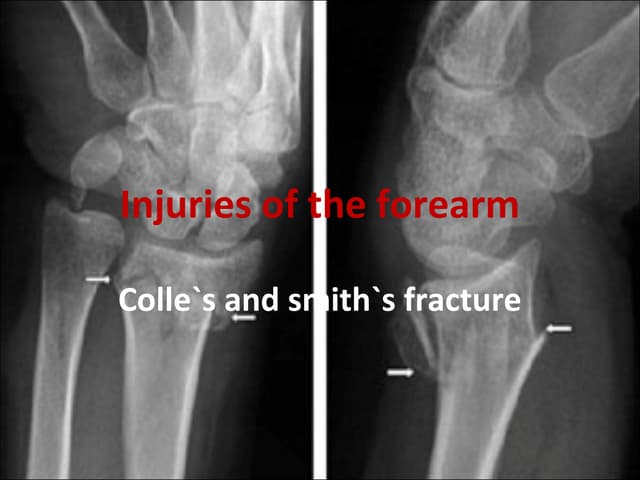

87. 87. • Common sites: fractures at the ends of a bone • E.g. supracondylar fracture of the humerus, Colles fracture. • Consequences: Deformity Shortening of the limb Limitation of movements

75. 75. LATE COMPLICATIONS DELAYED UNION When a fracture takes more than usual time to unite, it is said to have gone in ‘delayed union’.